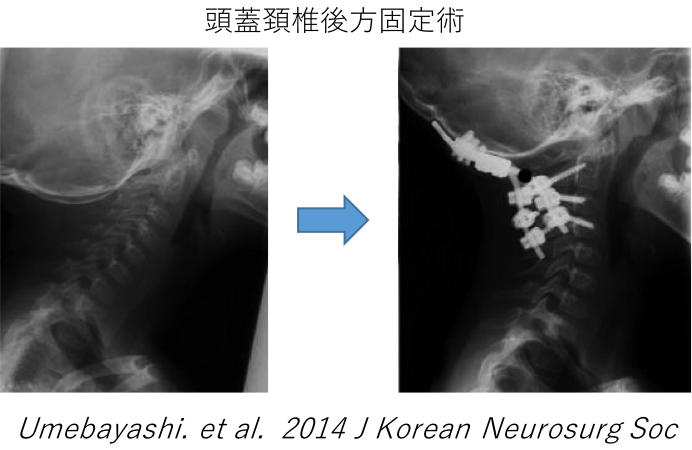

骨である頚椎自体の変形やずれ、不安定性がある場合は神経症状だけでなく、首の痛みや動いたときの症状の増悪などの症状をともないます。また、怪我・外傷によって同じことが起こり得ます。

この場合は骨である頚椎自体の治療のため、頚椎固定術が必要となります。椎弓根スクリューや外側塊スクリューを組み合わせた後方固定術を行います。必要があれば頭蓋骨からの連続した固定術も行います。

頸椎後方固定術 頭蓋頸椎後方固定術